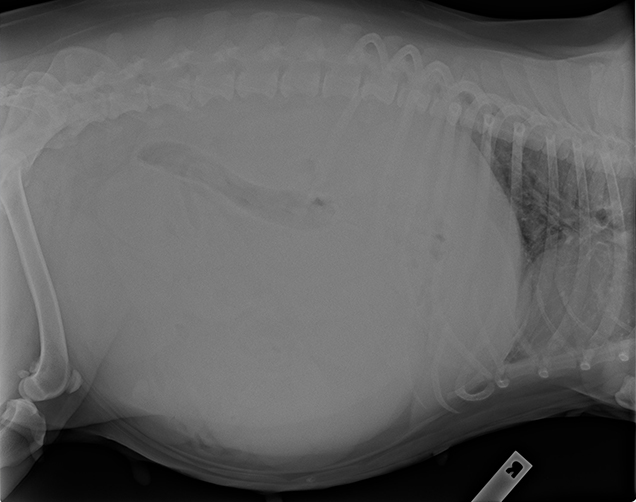

At seven years of age, poor Daisy had a ruptured pyometra which is an infection in her uterus. Daisy’s predicament was life threatening and could have been avoided. Pyometra is common disease in older female dogs. If left untreated it can lead to kidney failure, toxaemia, dehydration and even death! The best way to avoid it? Get your dog desexed!

Picked up by our Animal Ambulance, Daisy needed help fast! She was struggling to move, her breathing was rapid, and she had a lot of swelling in her abdomen.

Our veterinary team got to work by flushing Daisy’s abdomen in a very tricky surgery. The pus build-up for poor Daisy from a toxic pyometra was terrible to see. For a while it was touch and go for Daisy and our veterinary team were not sure she would pull through! We’re pleased to say that a few days after surgery, little Daisy was feeling much better and made a full recovery.